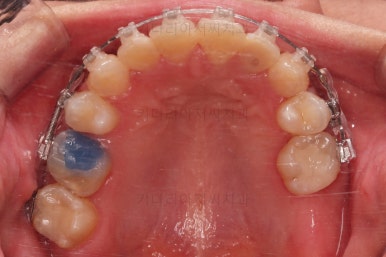

치열은 매우 가지런해졌고요.

추후에 발치 공간을 모아나가야 합니다.

윗니 앞니는 급한대로 신경치료 부터 진행했고, 최종 심미보철은 교정 후 미루었습니다.

마무리 못한 어금니 치료와 앞니 심미보철을 마무리 합니다.

앞니 심미보철까지 마무리 되었습니다.

물론 윗니 맨 뒤쪽 치아 한 군데는 임플란트가 들어가는 것이 가장 좋은데요.

이 부분은 여러 가지 사정들을 생각해서 좀 더 고민해 보시기로 했습니다.

중간 치아가 비어있다면 인접한 치아들이 쓰러진다거나 문제가 생길 수 있는데 맨 뒤 치아가 비어있다면 그것보다는 문제가 심각하진 않습니다.

당연히 임플란트가 들어가는 것이 여러 모로 좋긴 합니다.